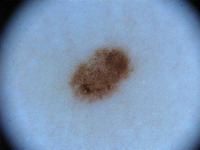

Dermatology Research: Researchers studying skin conditions could use this model to detect changes in the skin color, texture, or other characteristics over time. The model could help identify early signs of skin diseases and track their progression or regression.